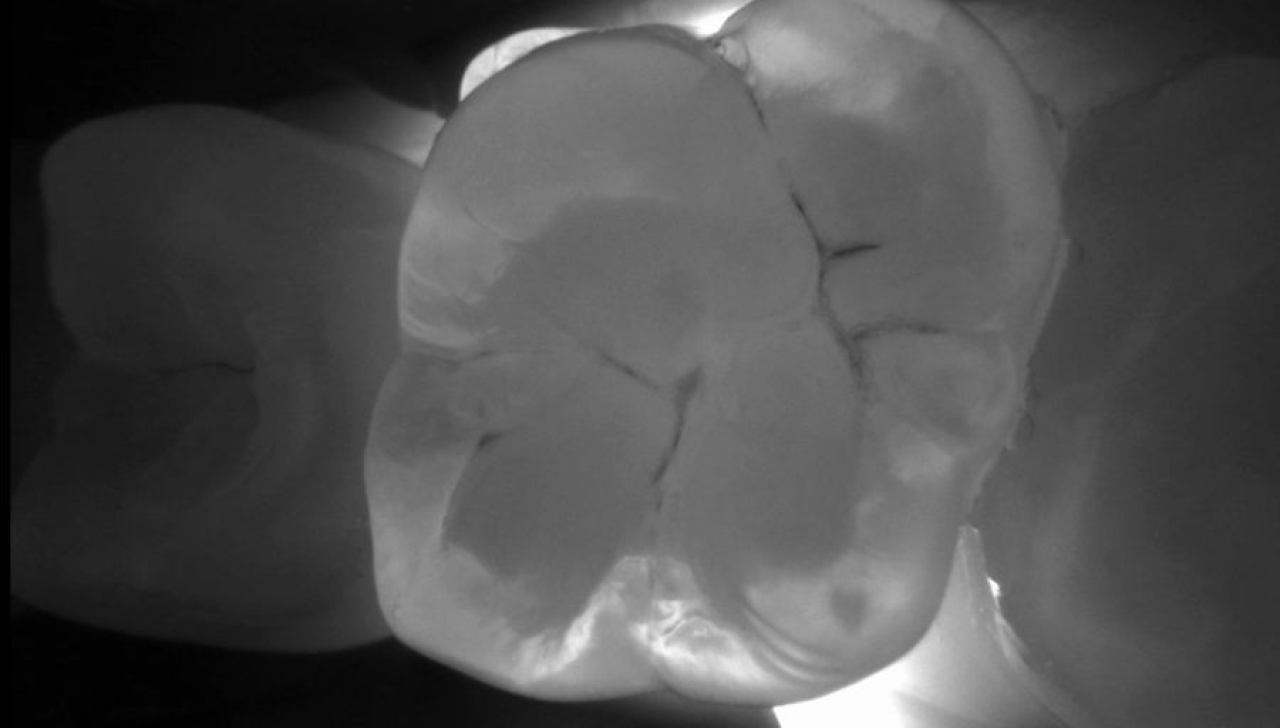

Dentalna dijagnostika

Marković Dental Clinic koristi najmoderniju rendgensku tehnologiju u dijagnostici orofacijalne regije.

Uz minimalnu dozu zračenja pacijenata i maksimalnu zaštitu, rendgenskim snimkama čeljusti možemo analizirati anatomske osobitosti zuba, čeljusti, patološke procese i tvorbe te visinu i širinu kosti čeljusti za planiranje dentalnih implantata.